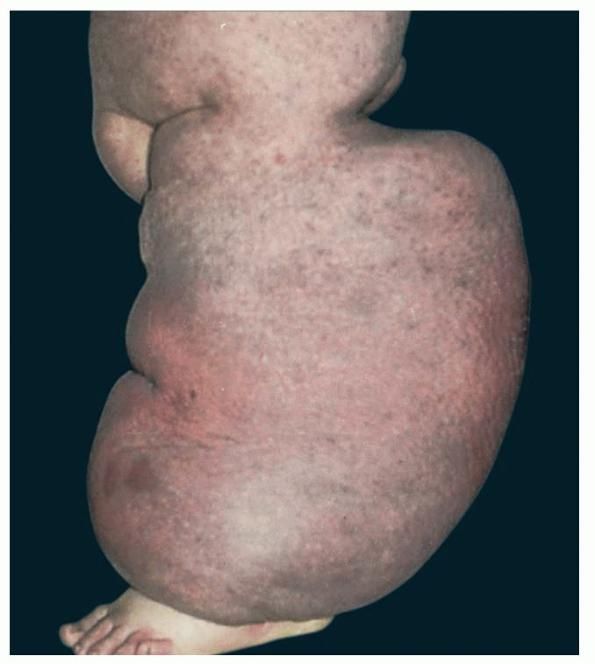

Worldwide lymphedema due to filariasis is estimated to affect between 90 and 100 million individuals . The microfilaria invade lymphatics, reproduce within the lymphatics, and damage local lymphatics and regional nodes, often resulting in hydroceles and scrotal swelling, classic components of filarial elephantiasis. In endemic areas, children may have subclinical disease that may be important to treat.

Prolonged lymphedema leads to fibrosis and epidermal hyperplasia with verrucous hyperkeratosis (Fig. 175-10). Ulceration rarely occurs, although the edema and hyperkeratotic changes may be profound. Lymphangiosarcoma, the Stewart-Treaves syndrome when associated with postmastectomy lymphedema, is the common lesion in chronically lymphedematous locations .